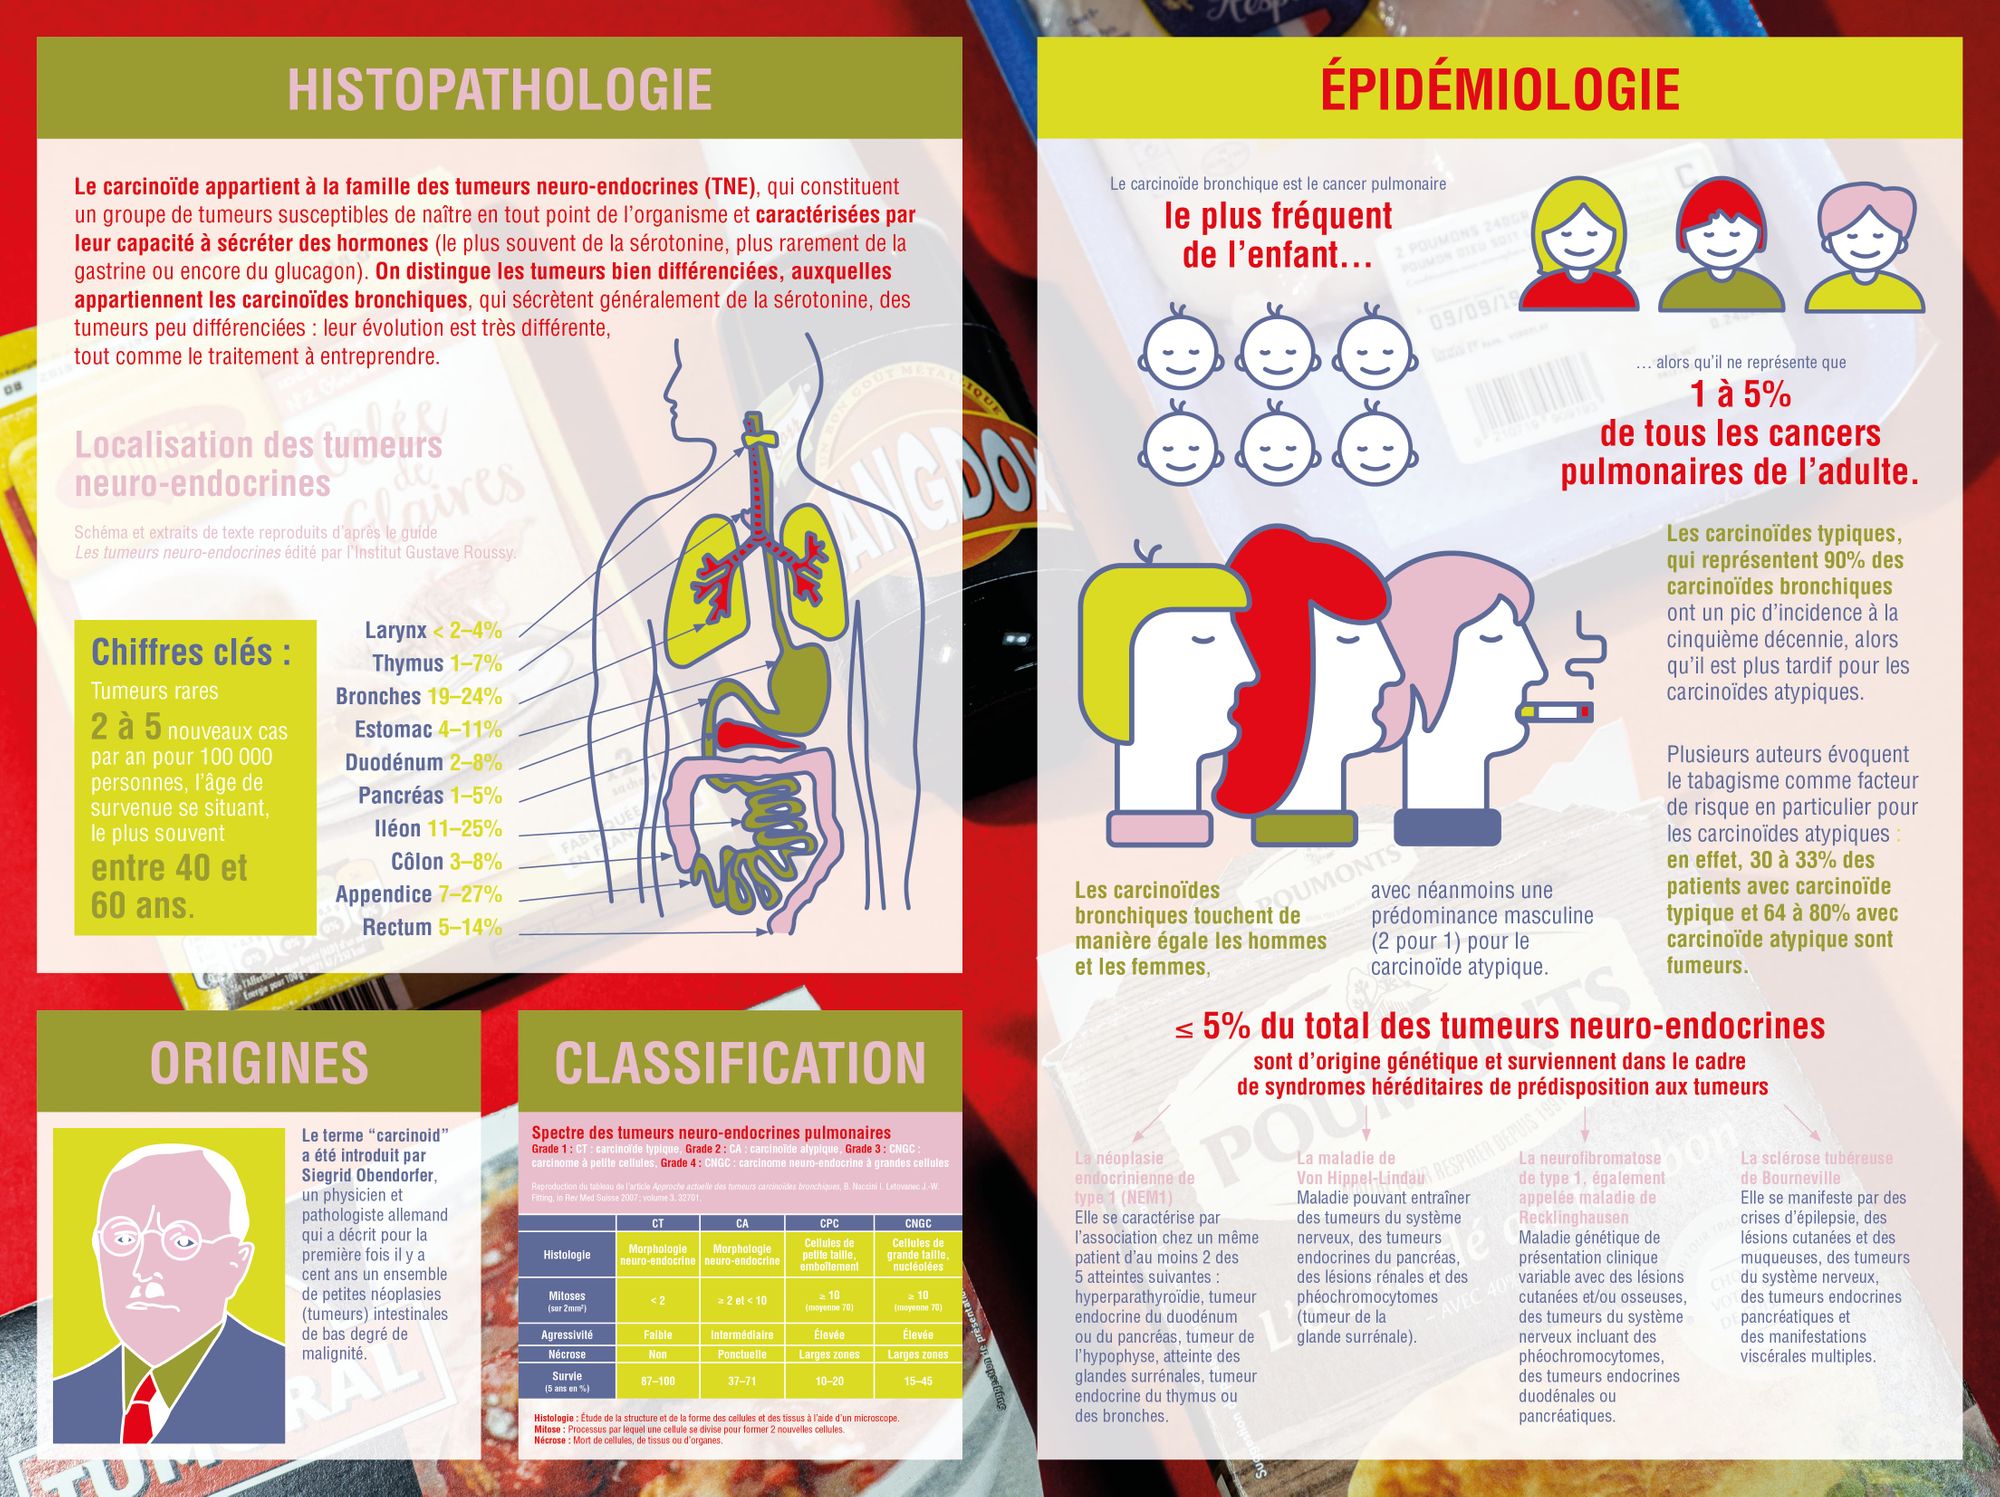

Camille Esayan est directrice artistique indépendante, et membre Wemind depuis 2018. Elle a le courage de nous livrer son histoire : la découverte d'une tumeur neuro-endocrine, un cancer qui a touché son poumon droit, alors qu'elle a 28 ans, l'opération, la peur, la rémission... puis la recherche d'un sens à cette épreuve qui l'amène à se donner une mission.

Ma vie bascule à l’été 2019 quand je découvre fortuitement être atteinte d’un cancer rare, une tumeur neuro-endocrine bronchique, alors que je me croyais à l’abri de la maladie.

Suite à cette heureuse nouvelle, je décide rapidement de mettre mes compétences en design graphique et en illustration au service des acteurs de la santé et du bien-être. Du cancer, plus particulièrement. C’est une évidence, et je choisis de la convertir en mission de vie. De cette décision naîtra Poumonoprix, un projet artistique à but non lucratif, dont l’ambition est de faire connaître les tumeurs neuro-endocrines bronchiques au grand public, de constituer une ressource pour de futurs malades et de devenir une véritable communauté d’échange et d’entraide autour de ce cancer. Aujourd’hui, je suis à la recherche de donateurs, privés comme publics, qui voudraient bien m’aider à concrétiser Poumonoprix au travers d’une exposition itinérante en France et d’une brochure imprimée.